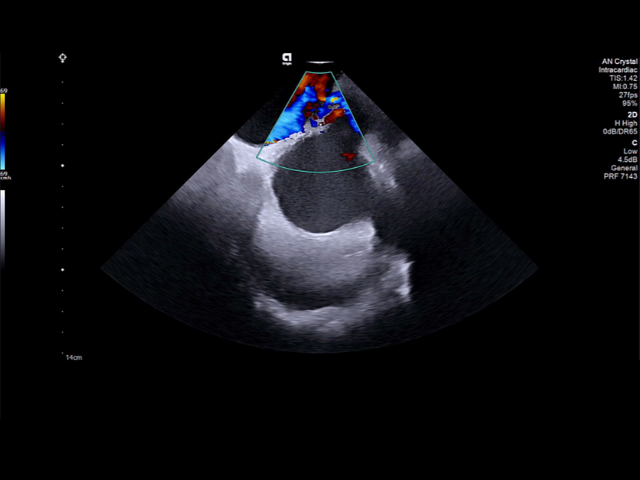

AcuNav Crystal

Powered by the ACUSON Origin ultrasound system, the AcuNav Crystal 2D ICE catheter delivers imaging clarity that opens new possibilities in structural heart and electrophysiology procedures. With accurate tissue contact and characterization, AcuNav Crystal supports emerging therapies like PFA and enables more precise treatments. Its consistent image quality helps detect complications earlier, helping to advance patient safety.